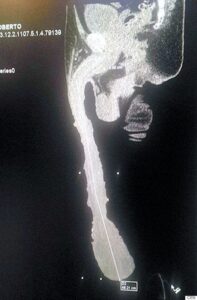

Ο 52χρονος Μεξικανός θα ήθελε μάλιστα το τεράστιο πέος του να γραφτεί στο βιβλίο των ρεκόρ γκίνες. Πρόσφατα μάλιστα υπεβλήθη σε ιατρική εξέταση και ακτινογραφία προκειμένου να αποδείξει ότι το μέγεθός του ήταν πραγματικό.

Ωστόσο, παρά την υποτιθέμενη επιβεβαίωση, ο γιατρός φέρεται να ισχυρίστηκε ότι το πέος του 52χρονου είναι μόνο 15,24 εκατοστά και όλο το υπόλοιπο είναι δέρμα που περισσεύει.

Η ακτινογραφία που έβγαλε ο 52χρονος Μεξικανός